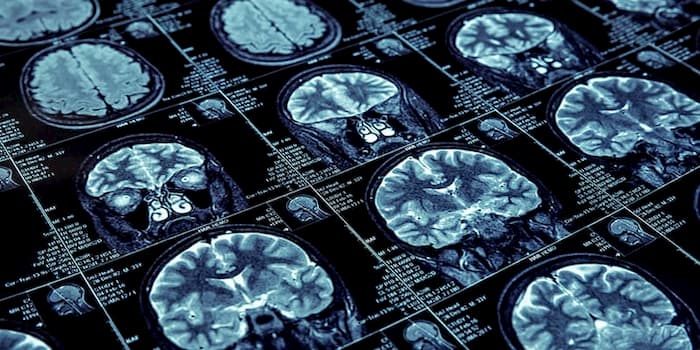

Understanding Migraine in Europe: Management Strategies and New Research Insights Migraine is a prevalent and often debilitating neurological condition affecting millions of individuals across Europe. Characterized by recurrent, severe headaches that can be accompanied by nausea, vomiting, and heightened sensitivity to light and sound, migraines pose significant challenges not only to those affected but also […]